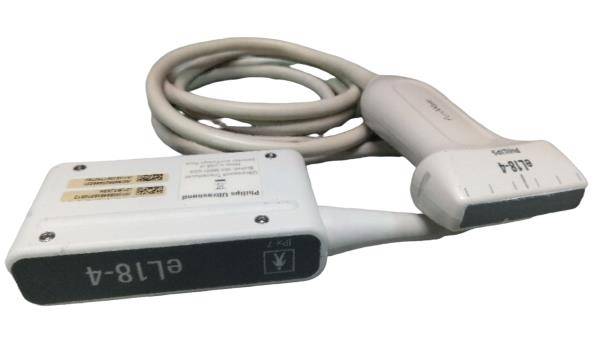

Acuson L382 3.5 MHz Linear Array Ultrasound Transducer Probe.USED TESTED

The Acuson L382 3.5 MHz Linear Array Ultrasound Transducer Probe is a used, tested, and fully functional device designed for high-resolution imaging. Ideal for vascular, musculoskeletal, and superficial tissue assessments, the 3.5 MHz frequency provides excellent detail for imaging of smaller structures. This transducer is compatible with Acuson ultrasound systems and is designed to deliver clear, reliable results for diagnostic applications. Despite being a used unit, it has been thoroughly tested to ensure it meets performance standards. It's a cost-effective solution for healthcare professionals seeking a quality ultrasound probe for detailed imaging.